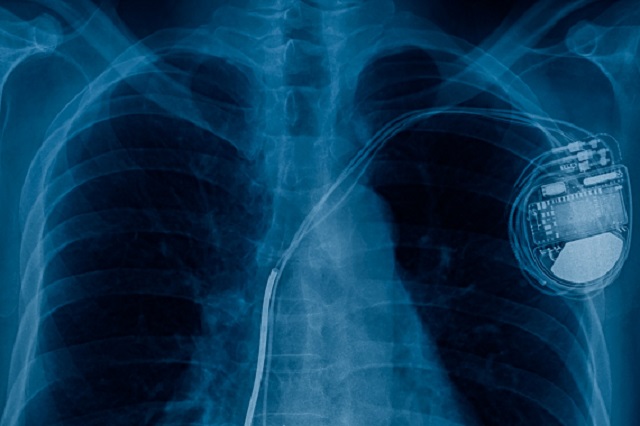

A pacemaker is a small electrical device, fitted in the chest or abdomen. It's used to treat abnormal heart rhythms that can cause your heart to either beat too quickly, too slowly or to miss beats. Some pacemakers can also help the chambers of your heart beat in time.

Pacemakers are powered by batteries, and currently the average battery lifespan is 6 to 7 years. Between 40 and 50,000 pacemakers are fitted every year in the UK.